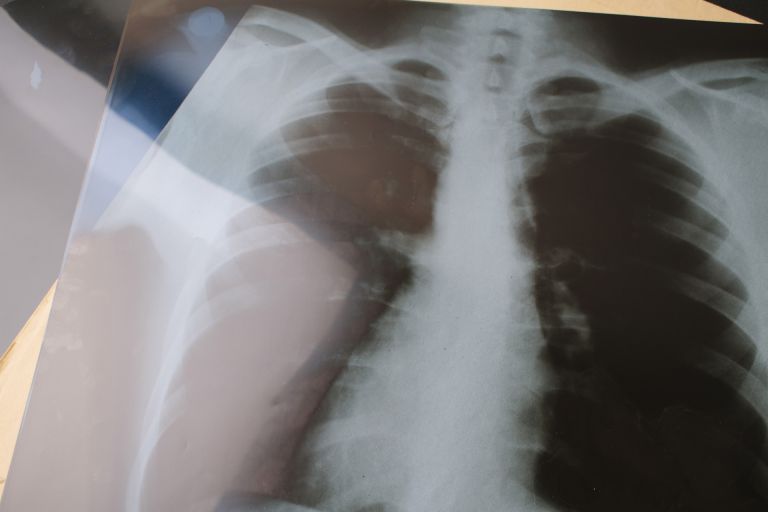

多くの人が往来することから、健康サポート体制への需要も高まっている。このエリアにはさまざまな診療科を持つ医療施設が点在しており、なかでも内科は幅広い世代にとって欠かせない存在である。内科は一般的な風邪やインフルエンザ、頭痛、腹痛などの症状から、糖尿病や高血圧、脂質異常症などの生活習慣病まで幅広い疾患を診療対象としている。さらにこの地域を行きかう人々の健康管理にとっても、内科の存在は非常に重要である。ビジネスパーソンや観光客、家族連れが急な体調不良を感じることは少なくなく、内科の外来診療があることで不安を和らげる役割を担っている。

医療体制についても、総合病院から地域密着型のクリニックまで幅広く配置されている。それぞれの医療施設には専門的な医師と看護師が在籍し、初期対応から慢性疾患の管理に至るまできめ細かな医療を提供している。例えば、定期健康診断や企業検診にも対応する施設もあり、地域企業の健康管理を支えている。また、一部の病院では電子カルテを導入して診療効率の向上や患者への説明の丁寧さを心掛けるなど、医療サービスの質の向上にも積極的に取り組んでいる。予約システムやオンライン相談窓口を設けて利便性を高めている施設も見受けられる。